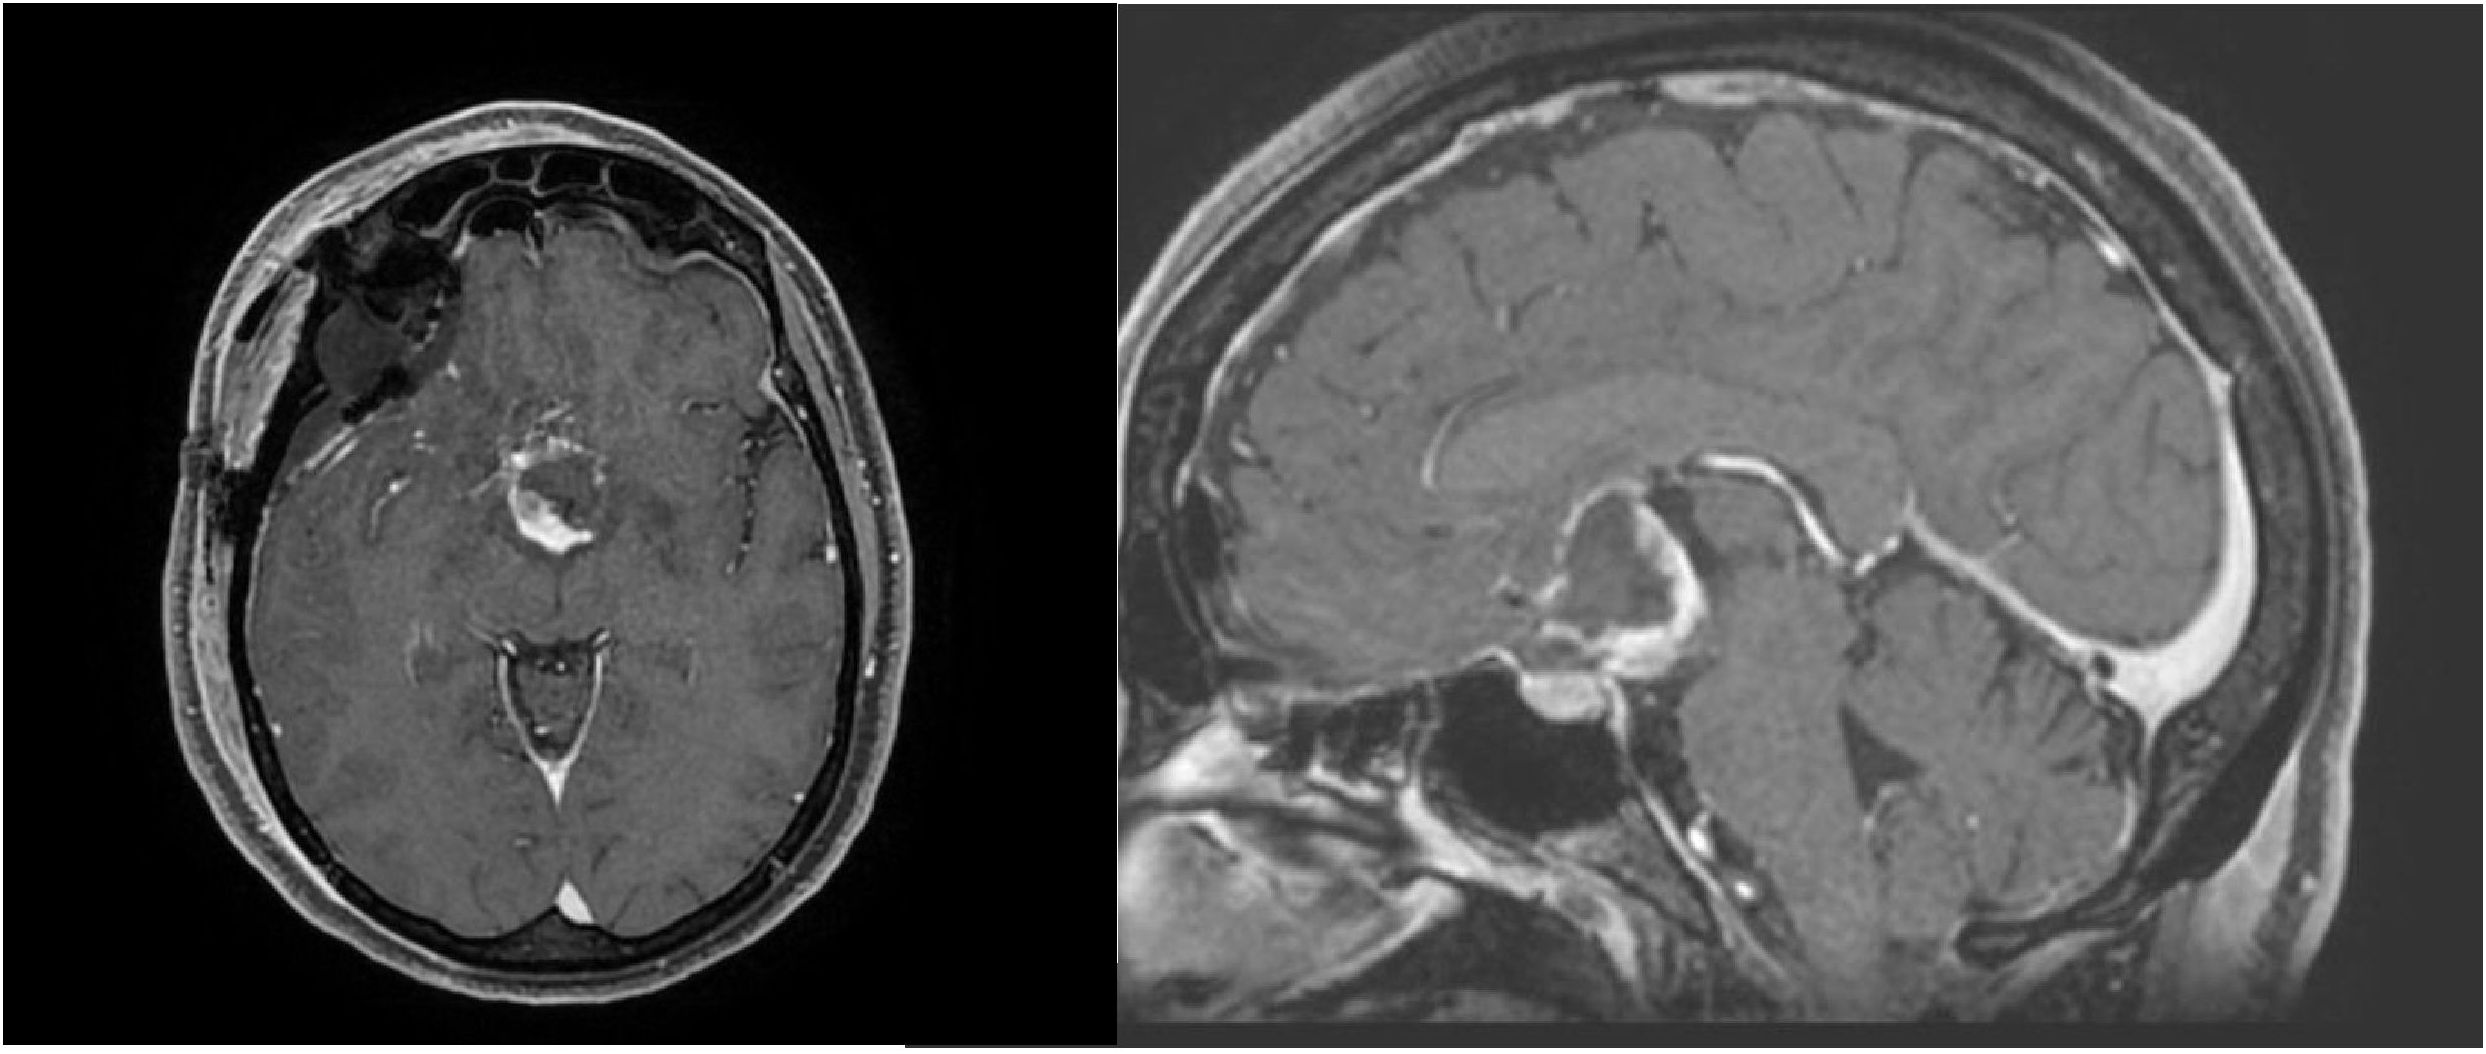

Background Chordoid glioma is a rare Grade II WHO brain tumor located in proximity of the third ventricle. Less than 100 cases are reported in the literature and surgery represents the main treatment option. Due to the typical location, complete surgical resection is uncommon, but the role of adjuvant radiotherapy is controversial. Methods Starting from a case report, we performed a literature review focused on the potential role of adjuvant radiotherapy for chordoid gliomas, reporting data on patients'characteristics, surgical approach and extent resection, radiotherapy technique and dose, and clinical outcomes. Results A total of 18 patients in 14 studies were identified, with a prevalent use of stereotactic treatments over conventional external beam radiotherapy, with doses respectively ranging between 11.5-18 Gy and 45-59.4 Gy, for a median time of local control of 26 months. Five patients developed disease recurrence after a median time of 22.4 months. In the case of the present study, the patient received adjuvant conventional radiotherapy (59.4 Gy/33 fx) is alive after 12 months of follow-up with no major side effects Conclusions From the available evidence, modern radiotherapy could be considered as a therapeutic tool able to conjugate less invasive surgical procedures with improved local control, thus reducing the risk of severe post-operative complications. Larger studies with longer follow-up are mandatory.